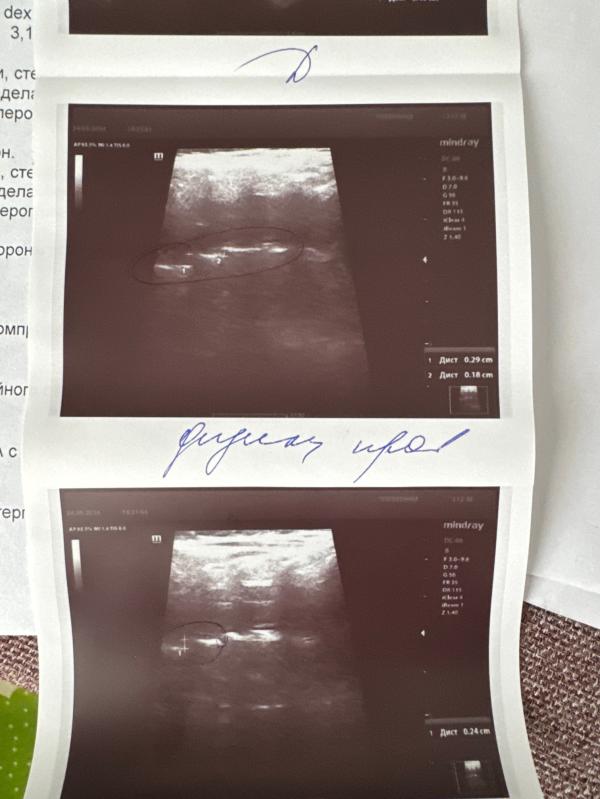

На узи у сына смешен 2ой позвонок, сказали обратится к неврологу для лечения

Офтальмолог обнаружил астигматизм и минус, посоветовал узи сделать и невролога пройти

У нас такая же проблема была по узи! Удалось быстро попасть к Кузьминой. Вправила все за минуту, да еще и в общей сложности нашла 4!!! смещения 🫣

К Панфиловой на мануальную терапию ходили 2 раза , все исправила . Плюс ходили на электрофорез и массаж - это уже невролог от поликлиники давала направление